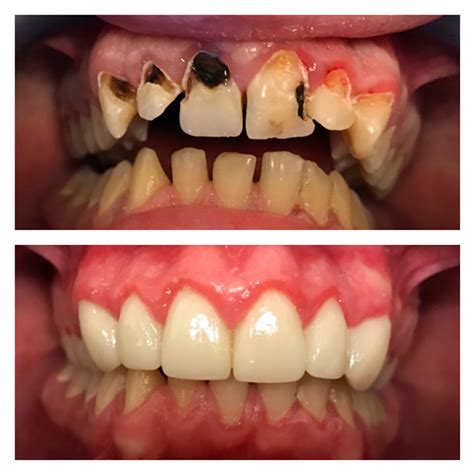

A major concern for patients is whether a root canal on front tooth will cause the tooth to turn dark or gray over time. While this can happen due to internal debris or the material used, modern techniques have significantly reduced the risk. If color changes do occur, your dentist can suggest cosmetic solutions such as internal bleaching, porcelain veneers, or a crown to match your natural tooth shade.